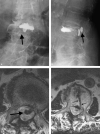

Case 2. Lumbar spine plain films and MR imaging were taken 8 months after vertebroplasty. A, AP view conventional radiograph of lumbar spine. B, Lateral view conventional radiograph of lumbar spine. C, Sagittal MR imaging. D and E, Axial MR imaging. There is hyperattenuated bone cement in L2 vertebral body and in the spinal canal (arrows) on the anteroposterior and lateral conventional radiographs (A and B). On the proton-weighted image (C) and T2-weighted image (D and E), bone cement is low in signal intensity. Bone cement is found inside the dural sac in C and D (arrow). Needle tract can be identified as a low-signal-intensity channel (arrows) in the vertebral body extending posteriorly to the epidural space (E). The technical flaw in this case was puncturing the epidural space with the needle allowing cement to extend posteriorly to the epidural space along the needle tract.

Fig 3.

Case 3. MR imaging taken 73 days after vertebroplasty (AD) and conventional radiographs of lumbar spine (E and F) taken 86 days after vertebroplasty. Dense bone cement is found in the anterior and posterior aspects of the vertebral body (white arrows), epidural space (short arrow), and intervertebral foramen (arrows). The technical flaw of this vertebroplasty was use of the wrong needle and possibly drilling past the epidural space. G, Arachnoid membrane shows active fibrosis and thickening (H&E stain). H, Epidural soft tissue shows fat necrosis and focal chronic inflammatory cell infiltration (H&E stain).